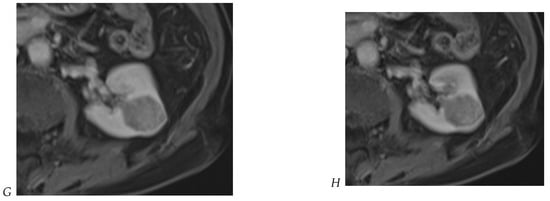

Figure 7.

Papillary renal cell carcinoma in the right kidney of a 75-year-old-woman. (A) Axial T2-weighted fast SE image shows a homogeneous 1.8 cm mass in the posterolateral region of the right kidney, with a lower SI compared to renal parenchyma. Transverse in-phase (B,C) opposed-phase MR images do not show a significant signal loss on the opposed-phase image. (D) The ADC map shows restriction of tumor diffusion into the renal mass. Transverse nonenhanced (E) and gadolinium-enhanced T1-weighted gradient-echo spoiled MR images in (F) corticomedullary, (G) nephrographic, (H) and delayed phase images show progressive enhancement without washout; the mass is hypovascular compared to the renal cortex.

The detection of macroscopic fat in a renal mass is essential because, in the absence of calcification, it is almost always characteristic of a classic (fat-rich) angiomyolipoma, the most common solid benign renal mass. The macroscopic fat component shows a loss of signal intensity on T1-weighted fat-suppressed images. Angiomyolipomas are also characterized by the presence of an India ink artifact on opposed-phase T1-weighted images at the junction of the mass and normal renal parenchyma, indicating a fat–water interface. T1-weighted gradient-echo inversion recovery imaging allows the detection of microscopic/intracytoplasmic fat. Microscopic intracellular fat is present in clear cell RCC (Figure 5), resulting in a signal drop on opposed-phase images. A signal drop has also been described in angiomyolipomas, including fat-poor angiomyolipomas (Figure 6). Gadolinium-enhanced T1-weighted three-dimensional fat-suppressed gradient-echo imaging is useful to assess the enhancement pattern in a renal mass. It allows the differentiation of hypervascular masses from hypovascular lesions with late and slow enhancement as seen in papillary RCC (Figure 7). T2-weighted sequences are essential for differentiating cystic renal masses from solid renal masses. The T2 signal intensity of a solid renal mass is also helpful in suggesting certain histologic subtypes of RCC. Both fat-poor angiomyolipomas (Figure 6) and papillary RCCs (Figure 7) have a low signal intensity on T2-weighted images, whereas other renal masses have an intermediate or high signal intensity. Several studies have suggested the potential utility of apparent diffusion coefficient (ADC) values to further characterize a renal mass [38]. Both fatty angiomyolipomas and papillary RCCs have low ADC values.